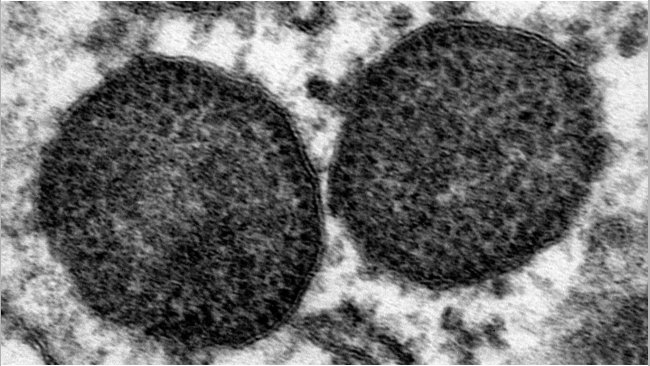

Es cierto que la recombinación es un fenómeno que se da en los circovirus. Se dan cambios de secciones entre virus y también pueden darse entre genotipos distintos. ¿Cómo afecta esto a la efectividad de la vacuna? Hay que tener en cuenta que las vacunas se hacen en base a la única proteína de cápside que presenta PCV-2, uno de los virus más simples que se conocen. Si pensamos en el caso de una hipotética recombinación entre el genotipo b y el d que afectara a toda esta sección, tampoco esperaríamos problemas de protección de la vacuna. Podría ser un problema si la recombinación afectara solo a una porción del genoma, pero las recombinaciones no se producen de forma aleatoria, tienen lugar en puntos concretos. Por todo ello, y teniendo en cuenta que tampoco se han hecho estudios específicos, a día de hoy no se considera que las recombinaciones sean una fuente de variación lo suficientemente grande como para que afecte a la capacidad de protección de las vacunas actuales. En estos casos esporádicos de granjas que vacunando frente a PCV-2 han presentado casos diagnosticados como circovirosis clínica, tampoco se han asociado a la presencia de virus recombinantes.